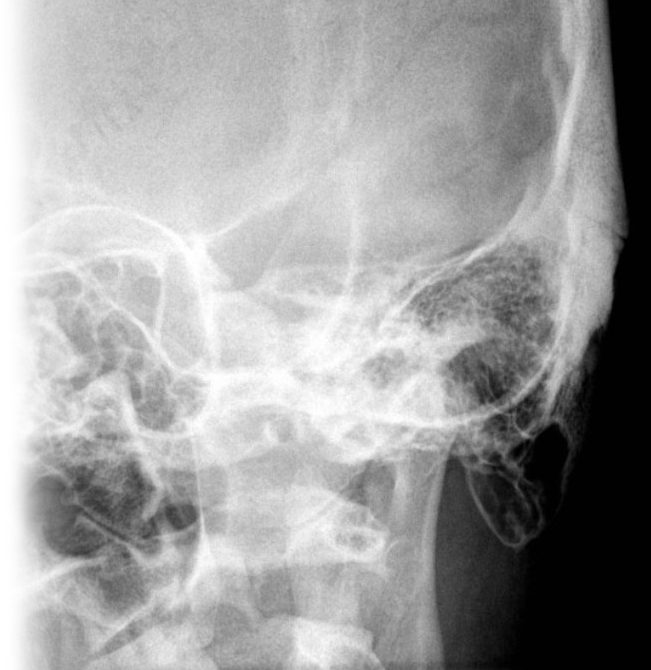

Рентгенография сосцевидных отростков – важный метод прицельного исследования сосцевидных отростков.

Диагностическая услуга выполняется в одной/двух проекциях. Сосцевидные отростки – выступы костей, которые расположены на боковых сторонах позвонках. Они играют важную роль в поддержании стабильности позвоночника и защите спинного мозга.